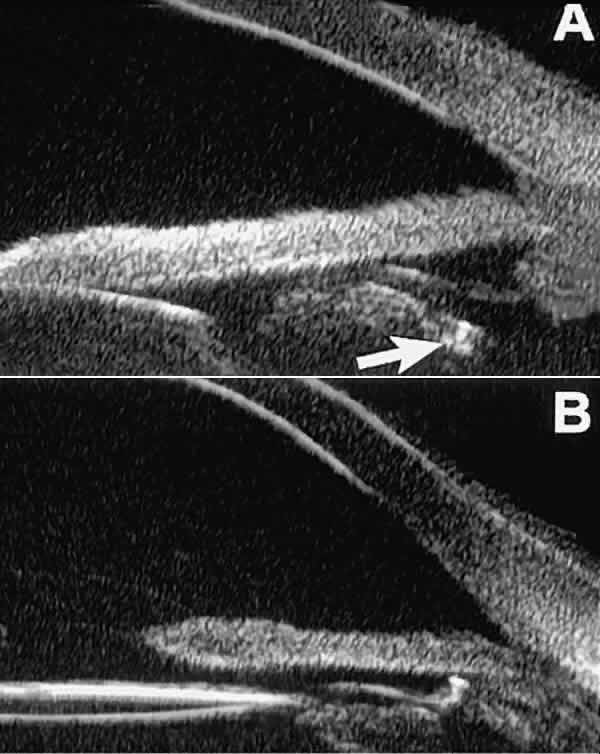

Postoperative UBM imaging of the anatomic changes caused by glaucoma surgery

often helps to explain mechanisms of success and failure of the

various surgical procedures (Fig. 12).3,4 After laser iridotomy, UBM can show whether the iridotomy is partial thickness (see Fig. 12A) or full thickness (see Fig. 12B) and whether the plane of curvature of the peripheral iris has changed

compared with the pretreatment findings. After trabeculectomy (see Fig. 12C), UBM can show whether the scleral aperture is patent or blocked internally, whether

the peripheral iridectomy is open or blocked, and whether

the filtering bleb is flat, shallow, or deep.9 After tube shunt surgery (see Fig. 12D), UBM can show the position of the tip of the tube and whether its orifice

is open or plugged.  Fig. 12. UBM features in glaucomatous eyes after treatment or filtering surgery. A. Incomplete peripheral iridectomy created by laser. B. Full-thickness peripheral iridectomy created by laser. C. Postoperative features of trabeculectomy including peripheral iridectomy, inner

scleral defect, thin residual scleral flap, and overlying conjunctival

filtering bleb. D. Tube shunt projecting radially into anterior chamber; note that the tube “shadows” deeper structures. Fig. 12. UBM features in glaucomatous eyes after treatment or filtering surgery. A. Incomplete peripheral iridectomy created by laser. B. Full-thickness peripheral iridectomy created by laser. C. Postoperative features of trabeculectomy including peripheral iridectomy, inner

scleral defect, thin residual scleral flap, and overlying conjunctival

filtering bleb. D. Tube shunt projecting radially into anterior chamber; note that the tube “shadows” deeper structures.

|